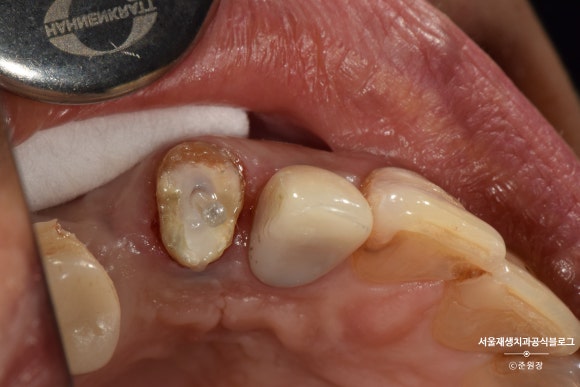

2주 후

연세가 조금 있으셨음에도 불구하고,

2주 후에 다행히 치아가 뼈에 단단히 결합된 상태로 재내원하셨습니다.

와이어를 제거했습니다.

최소한의 길이가 확보되긴 했지만 아직 크라운을 씌울 정도의 충분한 부피는 아닙니다.

나머지는 포스트와 레진의 도움을 받아 쌓아올립니다.